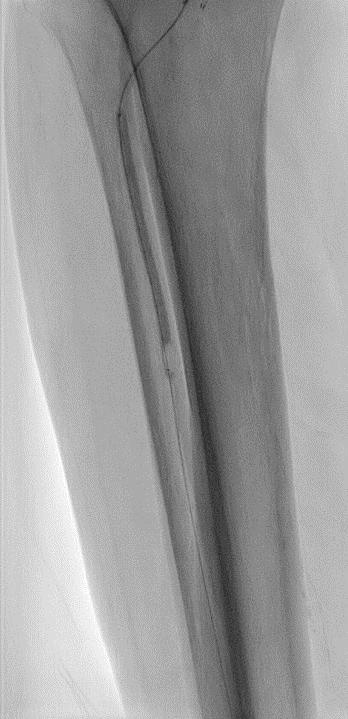

A 75-year-old female patient with diabetes and end-stage kidney disease (ESKD) presented with progressive right second toe swelling ulceration with gangrene and rest pain (Figure 1). There was extensive osteomyelitis and underlying tissue injury which required a planned amputation of the second toe. We were consulted prior to amputation for angiography, which demonstrated patent inflow vessels but severe BTK tibial disease. The baseline angiogram is shown in Figure 2. There was no inline flow to the foot, with occlusion of the anterior tibial, posterior tibial and peroneal arteries (Figure 2a). There was reconstitution of the peroneal artery, with partial filling of the posterior circulation via the posterior communicating artery. There was reconstitution of the anterior circulation with a visible small dorsalis pedis artery (Figure 2b).

Procedural overview

Given the angiosome of the tissue loss, we elected to pursue opening the anterior tibial CTO. Access with a 5F, 70cm sheath was used from a contralateral femoral approach. Using a 0.014” microcatheter and wire escalation, we were able to cross into the true distal lumen of the distal anterior tibial circulation using a 12-gram tipped guidewire (Figure 3a). A 2.5mm Shockwave E8 was used for multiple treatments along the entire length of the CTO segment (Figures 3b, 3c). Post IVL therapy, angiography showed brisk flow through the anterior tibial and into the distal anterior circulation of the foot (Figures 4a-c). This improvement in circulation allowed for this patient to undergo her planned second toe amputation with primary close (Figure 4d).